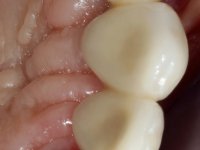

O estudo imagiológico para a colocação dos implantes, começou com a realização em laboratório de uma guia com dentes em sulfato de bário. Esta guia foi colocada em boca conjuntamente com marcas de referência coladas aos dentes, também em sulfato de bário. A guia foi estabilizada com cera mole. A TAC foi realizada com estas referências colocadas em boca. Após a realização da TAC foi feita uma impressão de arrasto em silicone. Esta impressão foi vazada a gesso em laboratório e posteriormente digitalizada. A digitalização do modelo com as referências foi sobreposta á imagem da TAC, permitindo uma planificação apurada na colocação dos implantes. Na planificação foi decidido colocar 2 implantes no local dos dentes 2.3 e 2.4 evitando-se a zona do 2.2 com pouco osso e o seio maxilar. Este estudo deu origem a uma guia cirúrgica que orientou a colocação dos implantes. Durante o período de osteo-integração a paciente utilizou a prótese removível rebasada com acondicionador de tecidos. A guia cirúrgica mostrou-se também útil na exposição dos implantes mostrando a sua localização precisa e orientando a incisão. A impressão definitiva foi realizada utilizando a técnica de moldeira aberta após eliminação do attachment. No laboratório foi confeccionada uma ponte metalo-cerâmica de 3 elementos com o elemento 2.2 em suspensão. A ponte após verificação e aprovação foi cimentada. A reabilitação apesar de pouco extensa (sem o elemento 2.6) mostrou-se capaz estetica e funcionalmente.